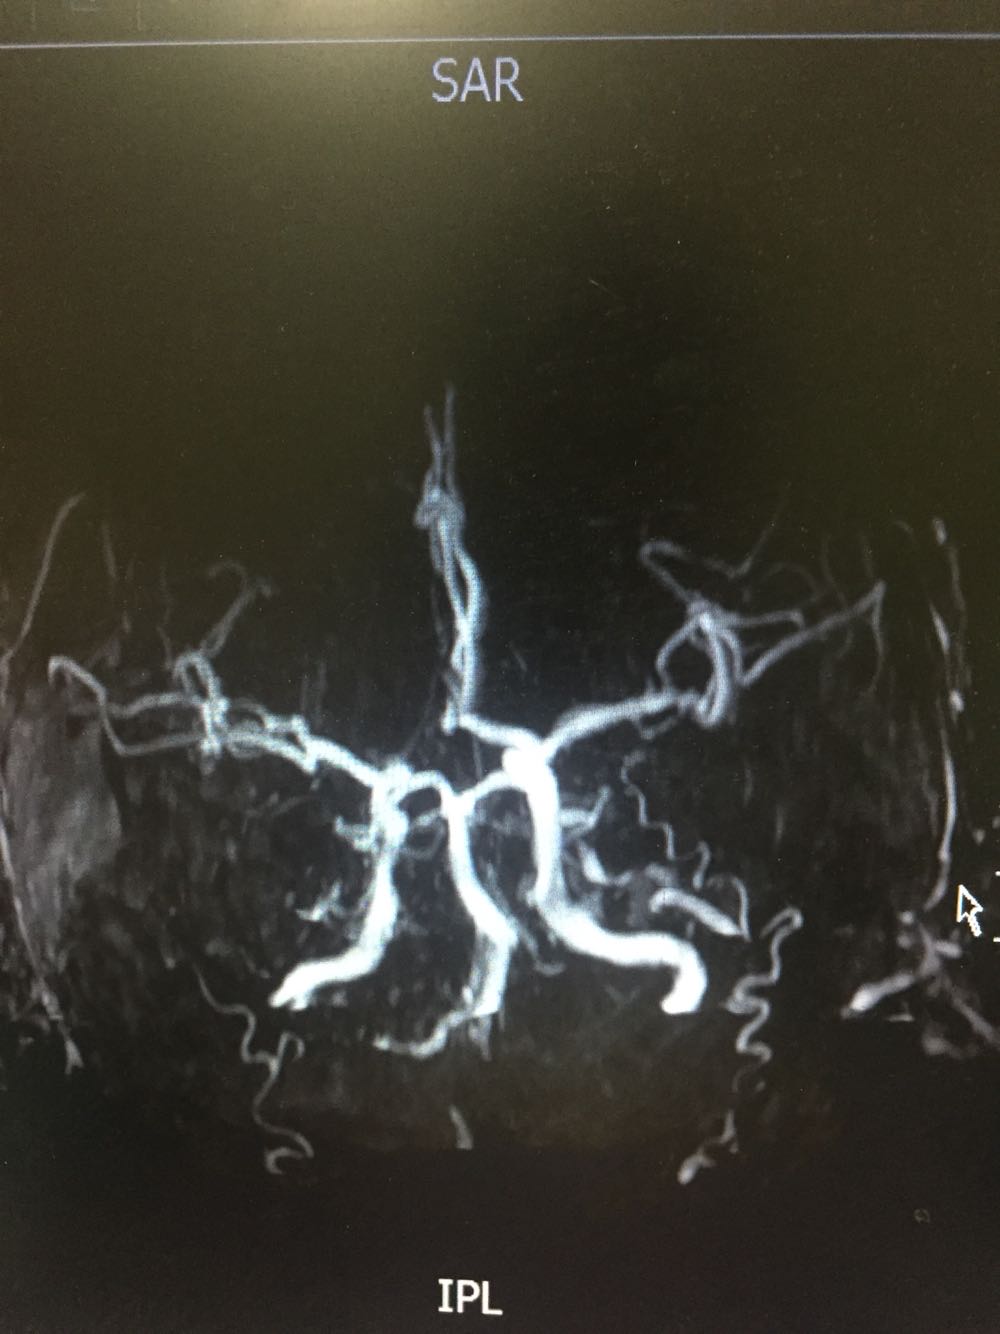

延髓梗死

54岁男患,主因左侧肢体无力伴言语含糊1日入院,既往否认高血压、糖尿病、冠心病 该患者于入院前1日吴明显诱因出现左侧肢体无力,伴有言语不清,不伴有头晕,不伴有恶心、呕吐,吴头痛,无视物旋转及视物双影,病程中无意识障碍及尿便障碍,不伴有耳鸣及听力下降,于当地医院诊断为脑梗死,静点奥扎格雷、小牛血去蛋白、血塞通、降纤酶,为求进一步诊治而来我院。

查体:血压178/102mmHg,神志清楚,构音障碍,查体合作,双瞳孔等大同圆,对光反射存在,双眼活动自如,左侧鼻唇沟浅,伸舌左偏,左侧肢体肌力3级,肌张力正常,腱反射对成,左侧感觉异常,左下肢Babinski(+)Chaddock(+),颈强(-),克氏征(-)头CT示脑梗死 甘油三酯5.69   总胆固醇6.32

延髓梗死、高血压、高脂血症 治疗改善循环、抗血小板聚集、脑保护、营养神经、调控血压、血脂对症治疗